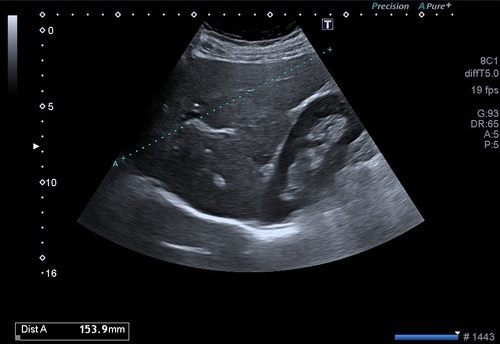

Batın ultrasonogafisi ile karaciğer, böbrekler, böbrek üstü bezleri, pankreas, safra kesesi, mesane, rahim, yumurtalıklar, prostat gibi belli başlı organlar değerlendirilir. Ayrıca bu organlar dışında batın içerisindeki sindirim sistemi organlarının ( mide, on iki parmak barsağı, ince ve kalın barsaklar) özellikle duvar yapıları ve önemli damarsal yapılar da değerlendirilir.

Batın ultrasonu ile karaciğer içerisindeki bir kist ya da kitlenin, karaciğerin yaygın hastalıklarının (hepatit, siroz vb.), karaciğer içerisindeki damar ya da safra yollarının hastalıklarının tanısı konulabilir. Safra kesesi taşları, safra çamuru, safra kesesi polipleri, safra yolları taşları ve safra kesesi duvarı kökenli kitleler ultrason incelemesinde görüntülenebilir.

Böbreklerin kist ya da kitleleri, böbrek taşları, böbrek kanallarında genişleme ve tıkanıklık, ciddi böbrek enfeksiyonları (pyelonefrit), böbrek üstü bezlerinin kitleleri ya da kalınlaşmaları, pankreasın enfeksiyonları, kist ya da kitleleri, pankreas kanalı tıkanıklıkları, mesane duvarı kitleleri, divertikülleri, mesane duvar enfeksiyonları(sistit), mesane taşları, rahim duvarından köken alan myomlar, rahimin içerisinden kaynaklanan kitleler, rahim kanalı hastalıkları, yumurtalıkların kist ya da kitleleri, içerisindeki follikül sayıları, endometrioma gibi kanamalı kitleler, prostat büyümesi, kitleleri gibi birçok hastalık batın ultrasonu ile değerlendirilir.

Batın içerisindeki mide ve barsakların duvar yapılarından kaynaklanan kitleler, barsak tıkanıklıkları, çocuklarda invajinasyon adı verilen barsakların iç içe geçmesi, apandisit, divertikülit, crohn gibi hastalıklar, batın içerisindeki ana damarların tıkanıklıkları ya da genişlemeleri, batın içerisindeki sıvı artışı ve kanama da bu yöntemle değerlendirilir.

Batın duvarını oluşturan kas tabakasındaki patolojiler ( göbek fıtıtğı, kasık fıtığı, kitleler, abseler vb.) batın ultrasonu ile değerlendirilir.

Ayrıca travma hastalarında, ana organlardaki yaralanmalar, batın içi kanama yada mide barsak sistemi yaralanmalarına bağlı batın içi havanın değerlendirilmesinde batın ultrasonu ilk tercihtir.